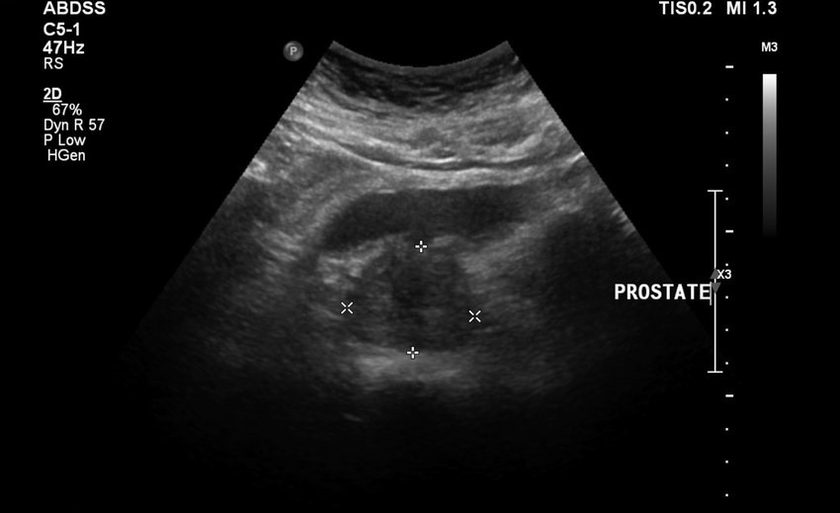

They made the rubberized rubberized calm, then the pain in the lower back added, the tests and the results of the ultrasound were bad.It was literally impossible to move away from the toilet, there was a feeling of heaviness in the groin area and in constant pain.The direct massage of the prostate was prescribed, which fell into panic.He started looking for other, less traumatic healing methods.